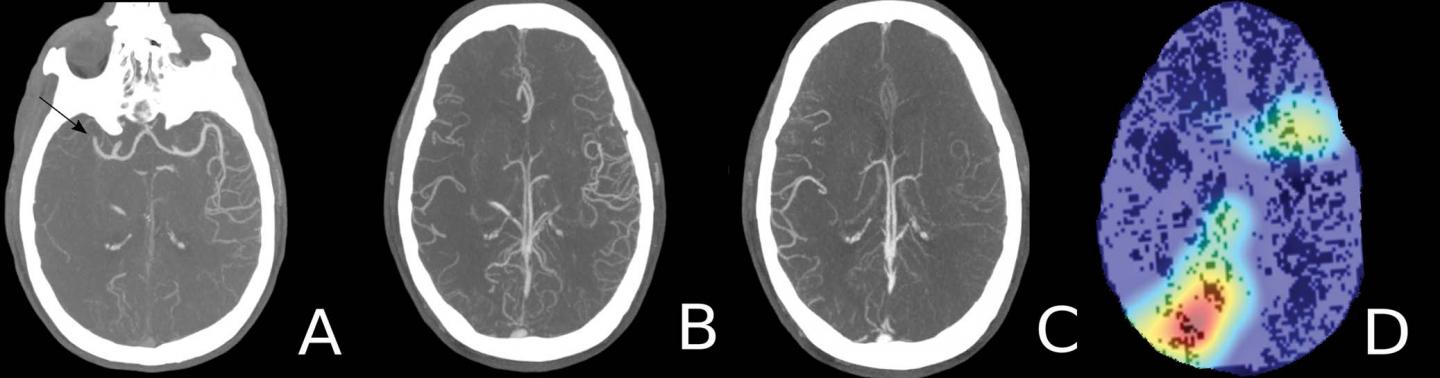

Working closely with Brown's computer science department, the researchers developed a deep learning model from scratch. They used a large sample of CTA examinations for patients with suspected acute ischemic stroke to train the algorithm to recognize the appearance of large vessel occlusions and distinguish it from other conditions. Preprocessing of the CTA exams included the creation of maximum intensity projection images to emphasize the contrast-enhanced vasculature. The researchers also used multiphase CTA, a newer approach that provides more comprehensive information than the single-phase technique.

When they tested the deep learning model on multiphase CTA examinations of 62 patients, the model detected all 31 large vessel occlusions for a sensitivity of 100%, a statistically significant improvement over the 77% sensitivity rate of single-phase CTA. The use of multiphase CTA contributed to the improved performance.

The study is the first to use multiphase CTA to look at occlusions in both the arteries of the front, or anterior, part of the head and neck and those in the back, or posterior.

"Posterior circulation occlusions have not been discussed much in machine learning literature," Dr. Stib said. "They're less common but have pretty profound clinical consequences if missed. It's important to have an algorithm that detects all categories of occlusion, both anterior and posterior."